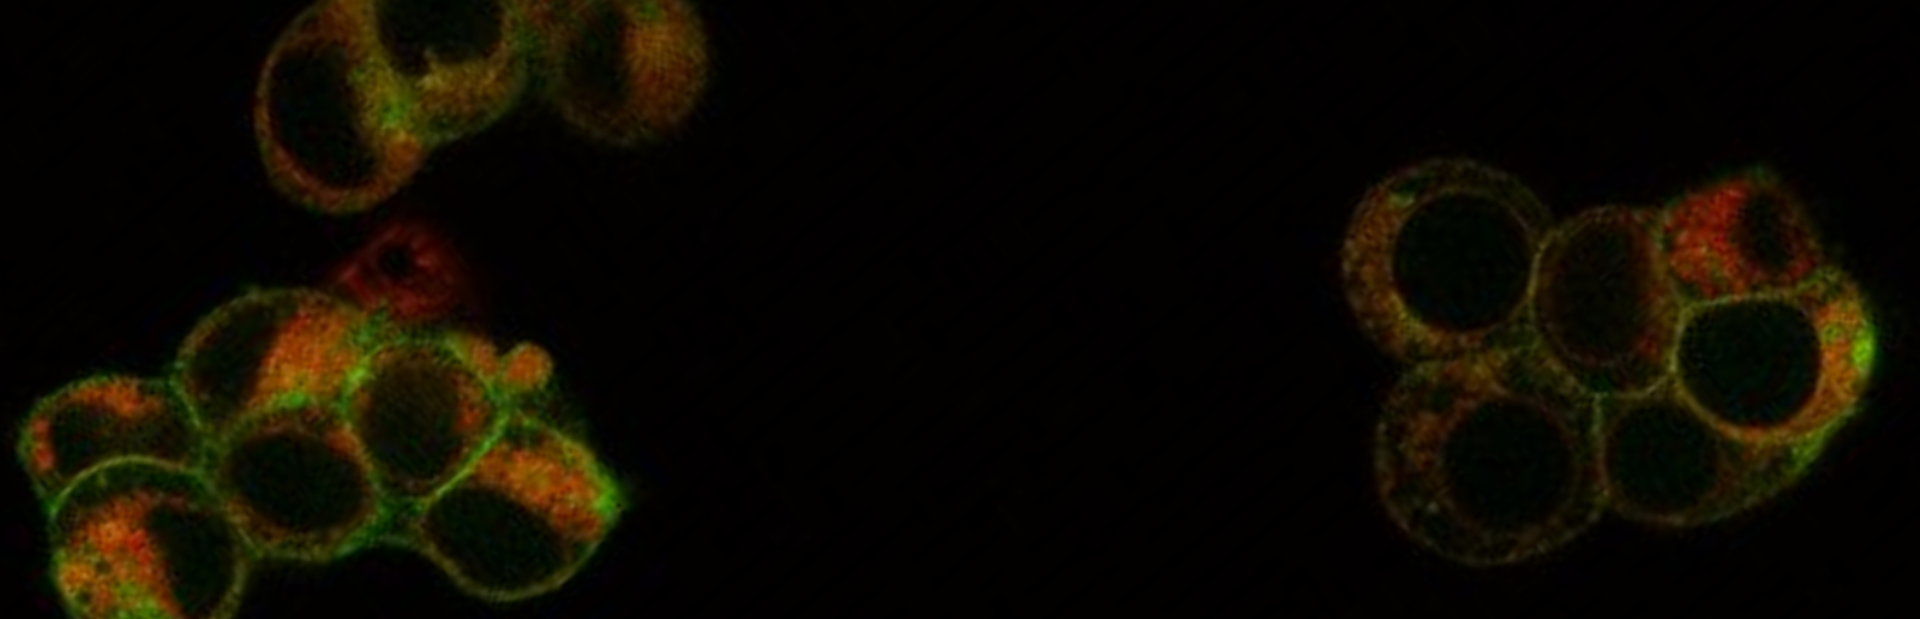

Figure 2: a. Insulin-producing pancreatic beta cells are highly sensitive to ferroptosis, and their loss is considered the origin of type 1 diabetes mellitus (T1DM), a classic example of a metabolic disease. Diabetes mellitus, not restricted to T1DM, is frequently associated with cardiovascular complications many of which originate from progressive atherosclerotic plaque formation. b. Cholesterol crystals and cells of both the innate and the adaptive immune systems are involved in atherosclerotic plaque formation, and ferroptosis may be amongst the many pathways that contribute to necrotic debris formation in these plaques. c. Upon atherosclerotic plaque rupture, commonly observed in patients suffering from metabolic syndrome which includes diabetes mellitus, myocardial infarction, stroke and other disorders associated with a perfusion-deficit or ischemia-reperfusion injury may occur. The necrosis observed in such tissues, particularly its cell death propagation, is known to be driven by ferroptosis. Treatment with various classes of ferrostatins was demonstrated to protect end organ damage in respective experimental models. (https://www.nature.com/articles/s41418-024-01350-1)